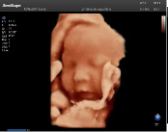

4容積探頭

積探頭是在二維圖像的基礎上,將連續(xù)采集的空間分布位置,經(jīng)過計算機重建算法,從而獲得完整的空間形態(tài)。

適用于:胎兒面部、脊柱和肢體等。

優(yōu)勢特點:快速獲取、掃查連續(xù)均勻、解剖結構顯示為容積數(shù)據(jù)、準確進行容積測量。